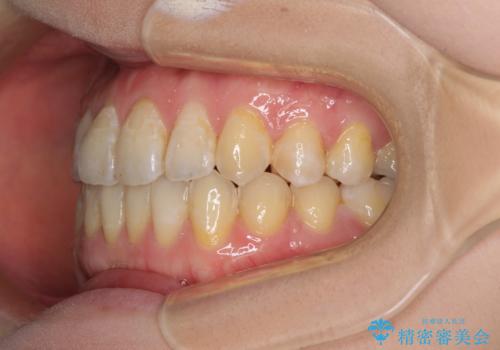

前歯のデコボコを治したい インビザラインによる矯正治療

- 前歯のデコボコを治したいとのことで来院された患者様です。

上下顎ともに歯列全体の後方移動とIPR(歯と歯の間を削る)によってデコボコが解消するように設計し、インビザラインにより治療を行うこととしました。